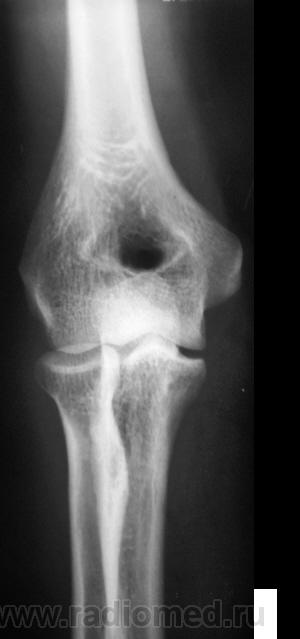

Травма. Пациент направлен на рентгенографию локтевого сустава.

Травма.    Пациент направлен на рентгенографию локтевого сустава. Исследование произведено.